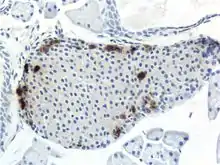

The pancreas serves multiple roles within mammalian organisms. It plays a role in the digestive system and the endocrine system making it an organ and a very important gland.[2] PP cells tend to located in the pancreatic islets, and are one of the rarer pancreatic cell types.[1] Some small clusters may also be found surrounded by exocrine pancreas.[3] They tend to be located in the duodenal part of the pancreas more medially.[3] Given their location in pancreatic islets along with their low population, they are able to respond efficiently to changes in blood sugar, nerve impulses, and chemical signaling through gap junctions or cellular signaling. PP cells show the highest concentration at the head of the pancreas.[1]

Through different microscopy techniques, the structural related details of PP cells have been able to be better understood. This is inclusive of how big they are, what their cellular membranes look like, the proteins associated with them, and even their size. PP cells are elongated cells. Another one of these details can be noted in insulins secretory granules, or container like buds, that store insulin within a cell. In PP cells, the size of the insulin granules are smaller and spherical and similar to those in alpha cells. This is noted in human PP cells, but different animals have been shown to have different sized granules compared to humans, like rodents. In cats and dogs, PP cells have large granules.[8] In rats, PP cells have few granules, similar to humans. In dogs, some PP cells are located in the walls of the antrum of the stomach.[3]